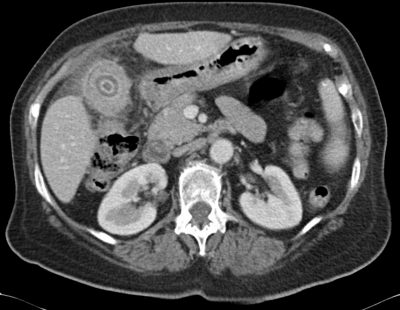

Los estudios por imagen evidenciaban colelitiasis y un proceso que afectaba a la mitad distal de la vesícula infiltrando localmente el lecho vesicular. Fue remitida para cirugía por sospecha de neoplasia. La tomografía axial computada y la resonancia nuclear magnética con colangioresonancia informaron: pérdida del plano de separación con el parénquima hepático y marcados cambios inflamatorios en la grasa adyacente, compatibles con colecistopatía crónica y con proceso inflamatorio agudo, pero sin poder descartar lesión neoplásica subyacente (ver Figuras 1 y 2).

Figura 1: TC abdominal con contraste (fase arterial). Se observa la vesícula de pared gruesa e irregular y con márgenes mal definidos con el parénquima hepático adyacente, que semeja infiltración.